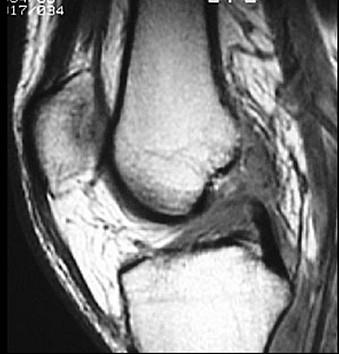

问题 男,37岁,右膝关节曾有外伤史,现感右膝关节部疼痛,请结合所提供的图像,选择最佳选项 ( )

选项 A、半月板损伤 B、后十字韧带撕裂 C、前十字韧带撕裂 D、胫骨骨折 E、未见异常

答案 C